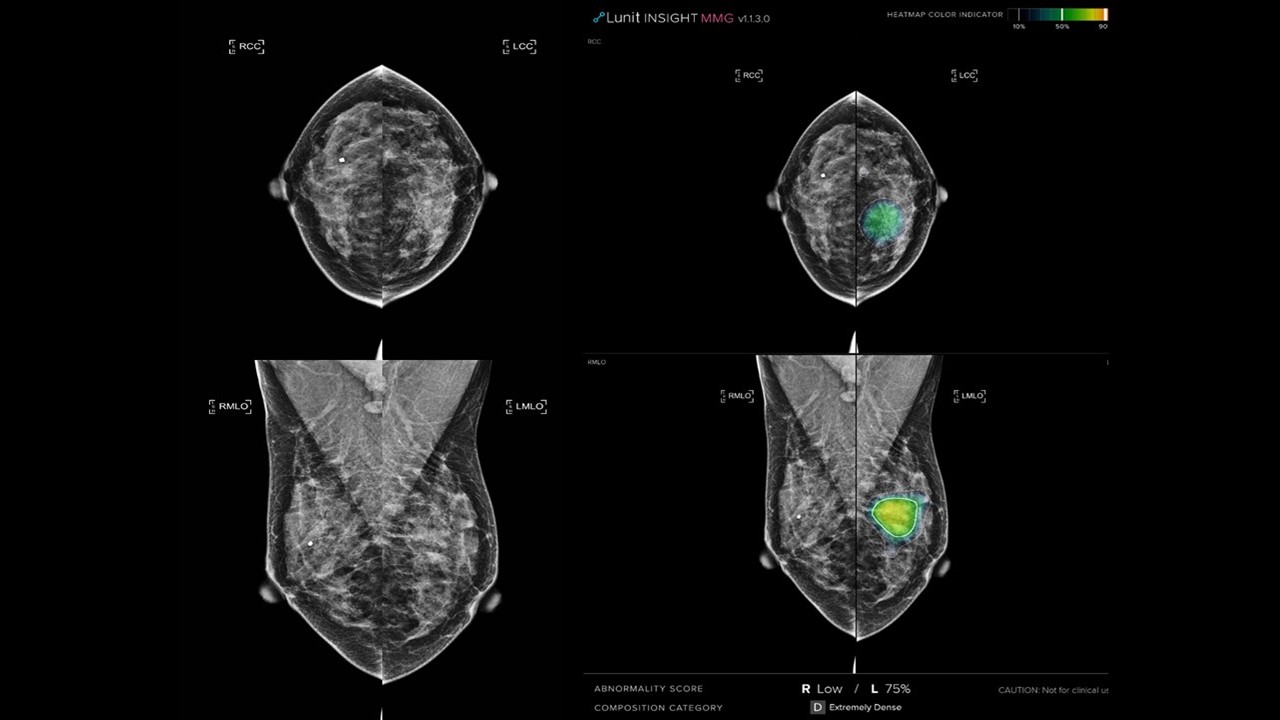

The AI-STREAM (Artificial Intelligence for Breast Cancer Screening in Mammography) study enrolled 25,008 women aged 40 and older, all participating in South Korea’s national breast cancer screening program. The final analysis involved 24,543 participants. Breast radiologists (BR) first interpreted the mammograms without AI assistance and then re-read them using AI-CAD (computer-assisted detection). Even with AI-aided, the radiologist made the final decision on whether a participant should be recalled for further evaluation. Additionally, a separate simulation study also compared the performance of general radiologists (GR) without and with AI assistance.

1. AI Alone vs. AI-Assisted Breast Radiologists:

• When used as a standalone tool, AI had a cancer detection rate (CDR) of 5.21 per 1,000 screenings, which was comparable to radiologists’ performance.

• However, AI alone had a higher recall rate (6.25%) than radiologists, meaning it flagged more cases that turned out not to be cancer. The study found that AI’s best performance came when it was used to assist breast radiologists rather than AI standalone.